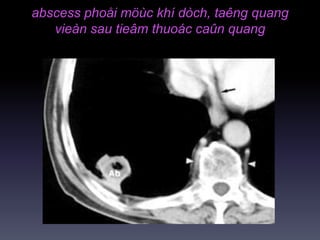

abscess phoåi möùc khí dòch, taêng quang

vieàn sau tieâm thuoác caûn quang

abscess phoåi möùckhí dòch, taêng quang vieàn sau tieâm thuoác caûn quang